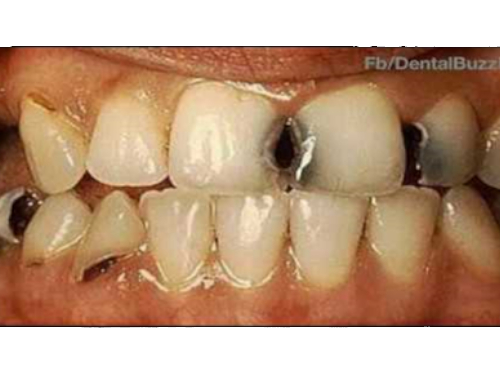

Early manifestation of decay is discolored surface of tooth. This is the demineralized portion of enamel (outer layer of tooth). This is mostly irreversible process requiring restorative treatment. If not treated at this stage, the decay may further involve dentin and pulp requiring more invasive procedure like root canal treatment.

Previously amalgam that is silver filling was widely used in dental practice, but due to its mercury component and unaesthetic features it is replaced by advanced tooth colored fillings.